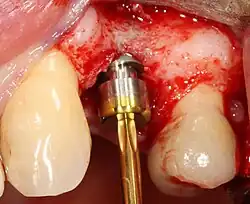

Область с единственным отсутствующим зубом

Через десну делается разрез, и лоскут ткани откидывается, чтобы показать кость челюсти.

Как только кость обнажена, серия упражнений создаёт и постепенно увеличивает участок (называемый остеотомией) для установки имплантата.

Крепление имплантата превращается в остеотомию. В идеале он полностью покрыт костью и не имеет движения внутри кости.